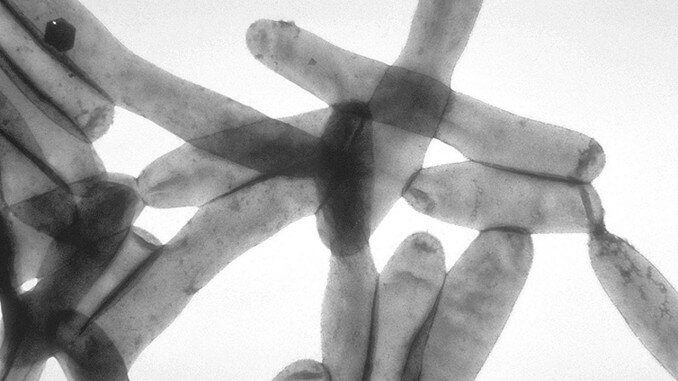

Bei Temperaturen von 20-55 °C können sich Legionellen vermehren

Das Bundesumweltamt warnt davor, die Warmwassertemperaturen dauerhaft unter 55 °C zu fahren. Denn dann haben Legionellen beste Bedingungen sich zu vermehren. Wir erinnern uns: es kam häufig vor, dass sich die Gäste ganzer Hotels mit Legionellen infizierten und erkrankten. Die Bakterien vermehren sich am schnellsten in stehendem Wasser (Speicher) mit Wassertemperaturen von 35 bis 45 °C. Das bedeutet, dass Energiesparen an dieser Stelle evtl. keine gute Idee ist.